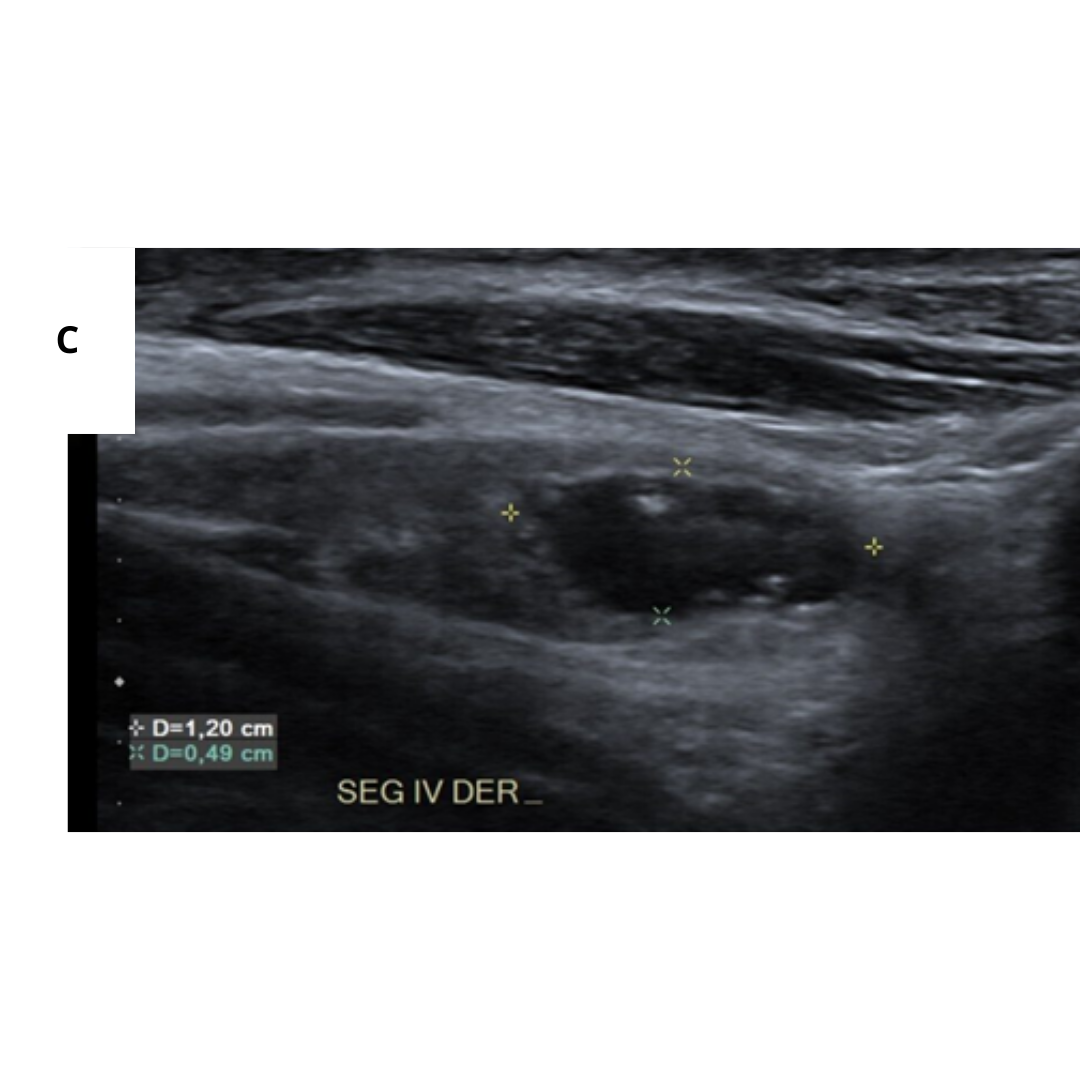

Fig2. A) Masa hipoecoica mal definida, con microcalcificaciones difusas y dispersas que ocupaban toda la glándula. B) Ganglio linfático cervical aumentado de tamaño con múltiples microcalcificaciones dispersas (2).

Fig3. (A) Numerosas microcalcificaciones en todo el lóbulo derecho como una “tormenta de nieve” sin nódulos en la sección longitudinal de la tiroides. (B) Patrón en “tormenta de nieve” en el lóbulo derecho con un nódulo hipoecoico de borde mal delimitado en el corte longitudinal de la tiroides (8).

Fig4. (A) En lóbulo tiroideo derecho, 1/3 medio, se visualiza nódulo sólido, hipoecogénico, mal delimitado con múltiples calcificaciones puntiformes en su interior (cuerpos de Psamoma). (B) Estas también se presentan de manera difusa periféricas al nódulo. (C) En Región cervical derecha, GIV, se visualiza ganglio cervical aumentado de tamaño, con múltiples imágenes puntiformes hiperecogénicos en su periferia e interior sugerente de microcalcifcaciones.